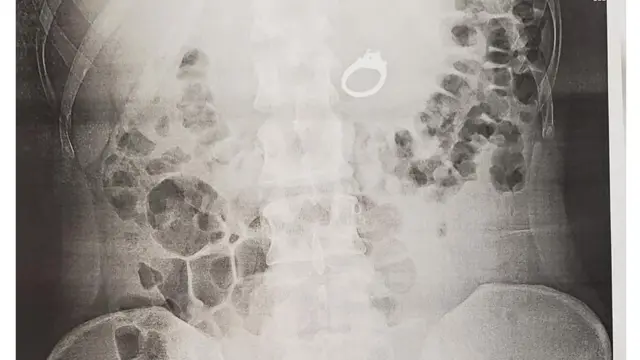

Qorannoon carallaa [X-ray] qubeellaa kaaraatii 2.4 tahu garaa ishee keessatti agarsiise.